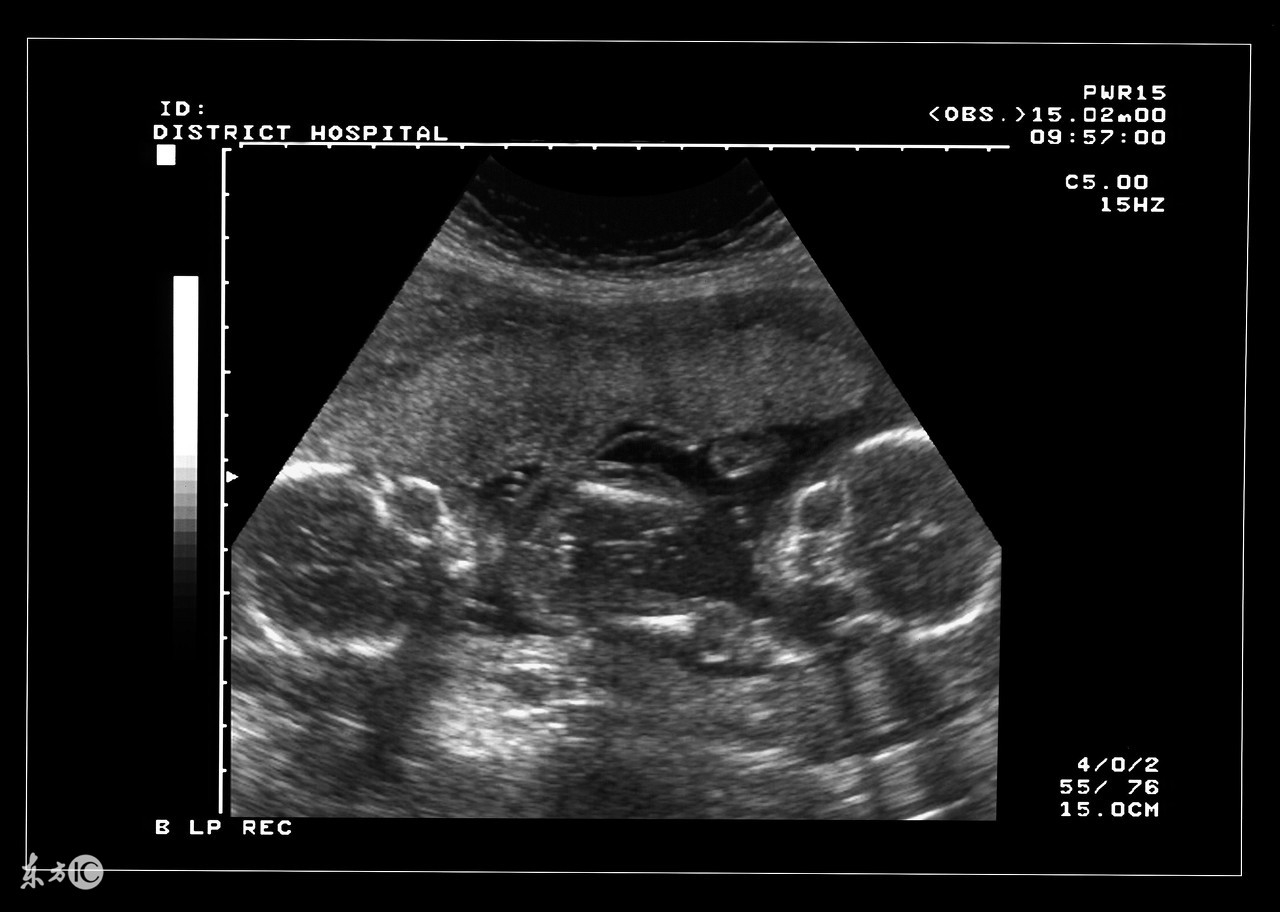

双胞胎确实是一件可想而不可求的事情,当孕妇怀上双胞胎或者多胎后,使母体长期处于超负荷的状态,在预产期到来之前,准妈妈需要就是否实施剖腹产的问题预先与家人和医生达成一致,并为此做好准备。大家都知道,自然分娩是最理想不过的,但实际上为了确保安全,大部分多胞胎最终实施的都是剖腹产。

双胎妊娠检查非常重要。由于双胎孕妇比一般孕妇子宫明显增大,这不仅增加了孕妇身体的负担,还由于对其心、肺及下腔静脉的压迫而容易产生心慌、呼吸困难及下肢浮肿等不适。双胎妊娠出现妊娠合并症者也较多,其妊高娠的发生率明显高于一胎妊娠,所以双胎妊娠者要听从医嘱,按期去医院接受检查。

双胎妊娠由于子宫腔相对狭窄胎盘血液循环障碍,其流产发生率较单胎妊娠高2—3倍,因此应加强孕期保护与监护。若一胎发生死胎,另一胎仍可继续生长发育,死亡的胎儿将被吸收或挤压成纸样儿随正常胎儿娩出,不必担心害怕,更不要引产终止妊娠。因双胎妊娠子宫过度膨胀,易发生早产,故应于中期妊娠后关注休息,避免房事,并提前4周做好分娩前的准备工作。由于妊娠的并发症尤其是妊高娠的发生率比较高,从母子安全考虑,应在预产期即住院待产,以免发生早产或其他不测。